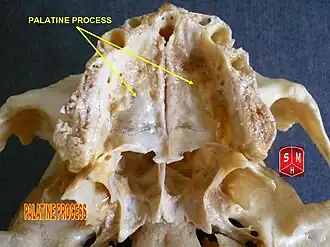

Palatine process of maxilla

| Palatine process of maxilla | |

|---|---|

Inferior surface of maxilla. The bony palate and alveolar arch. (Palatine process labeled at bottom right.) | |

Inferior surface of maxilla. | |